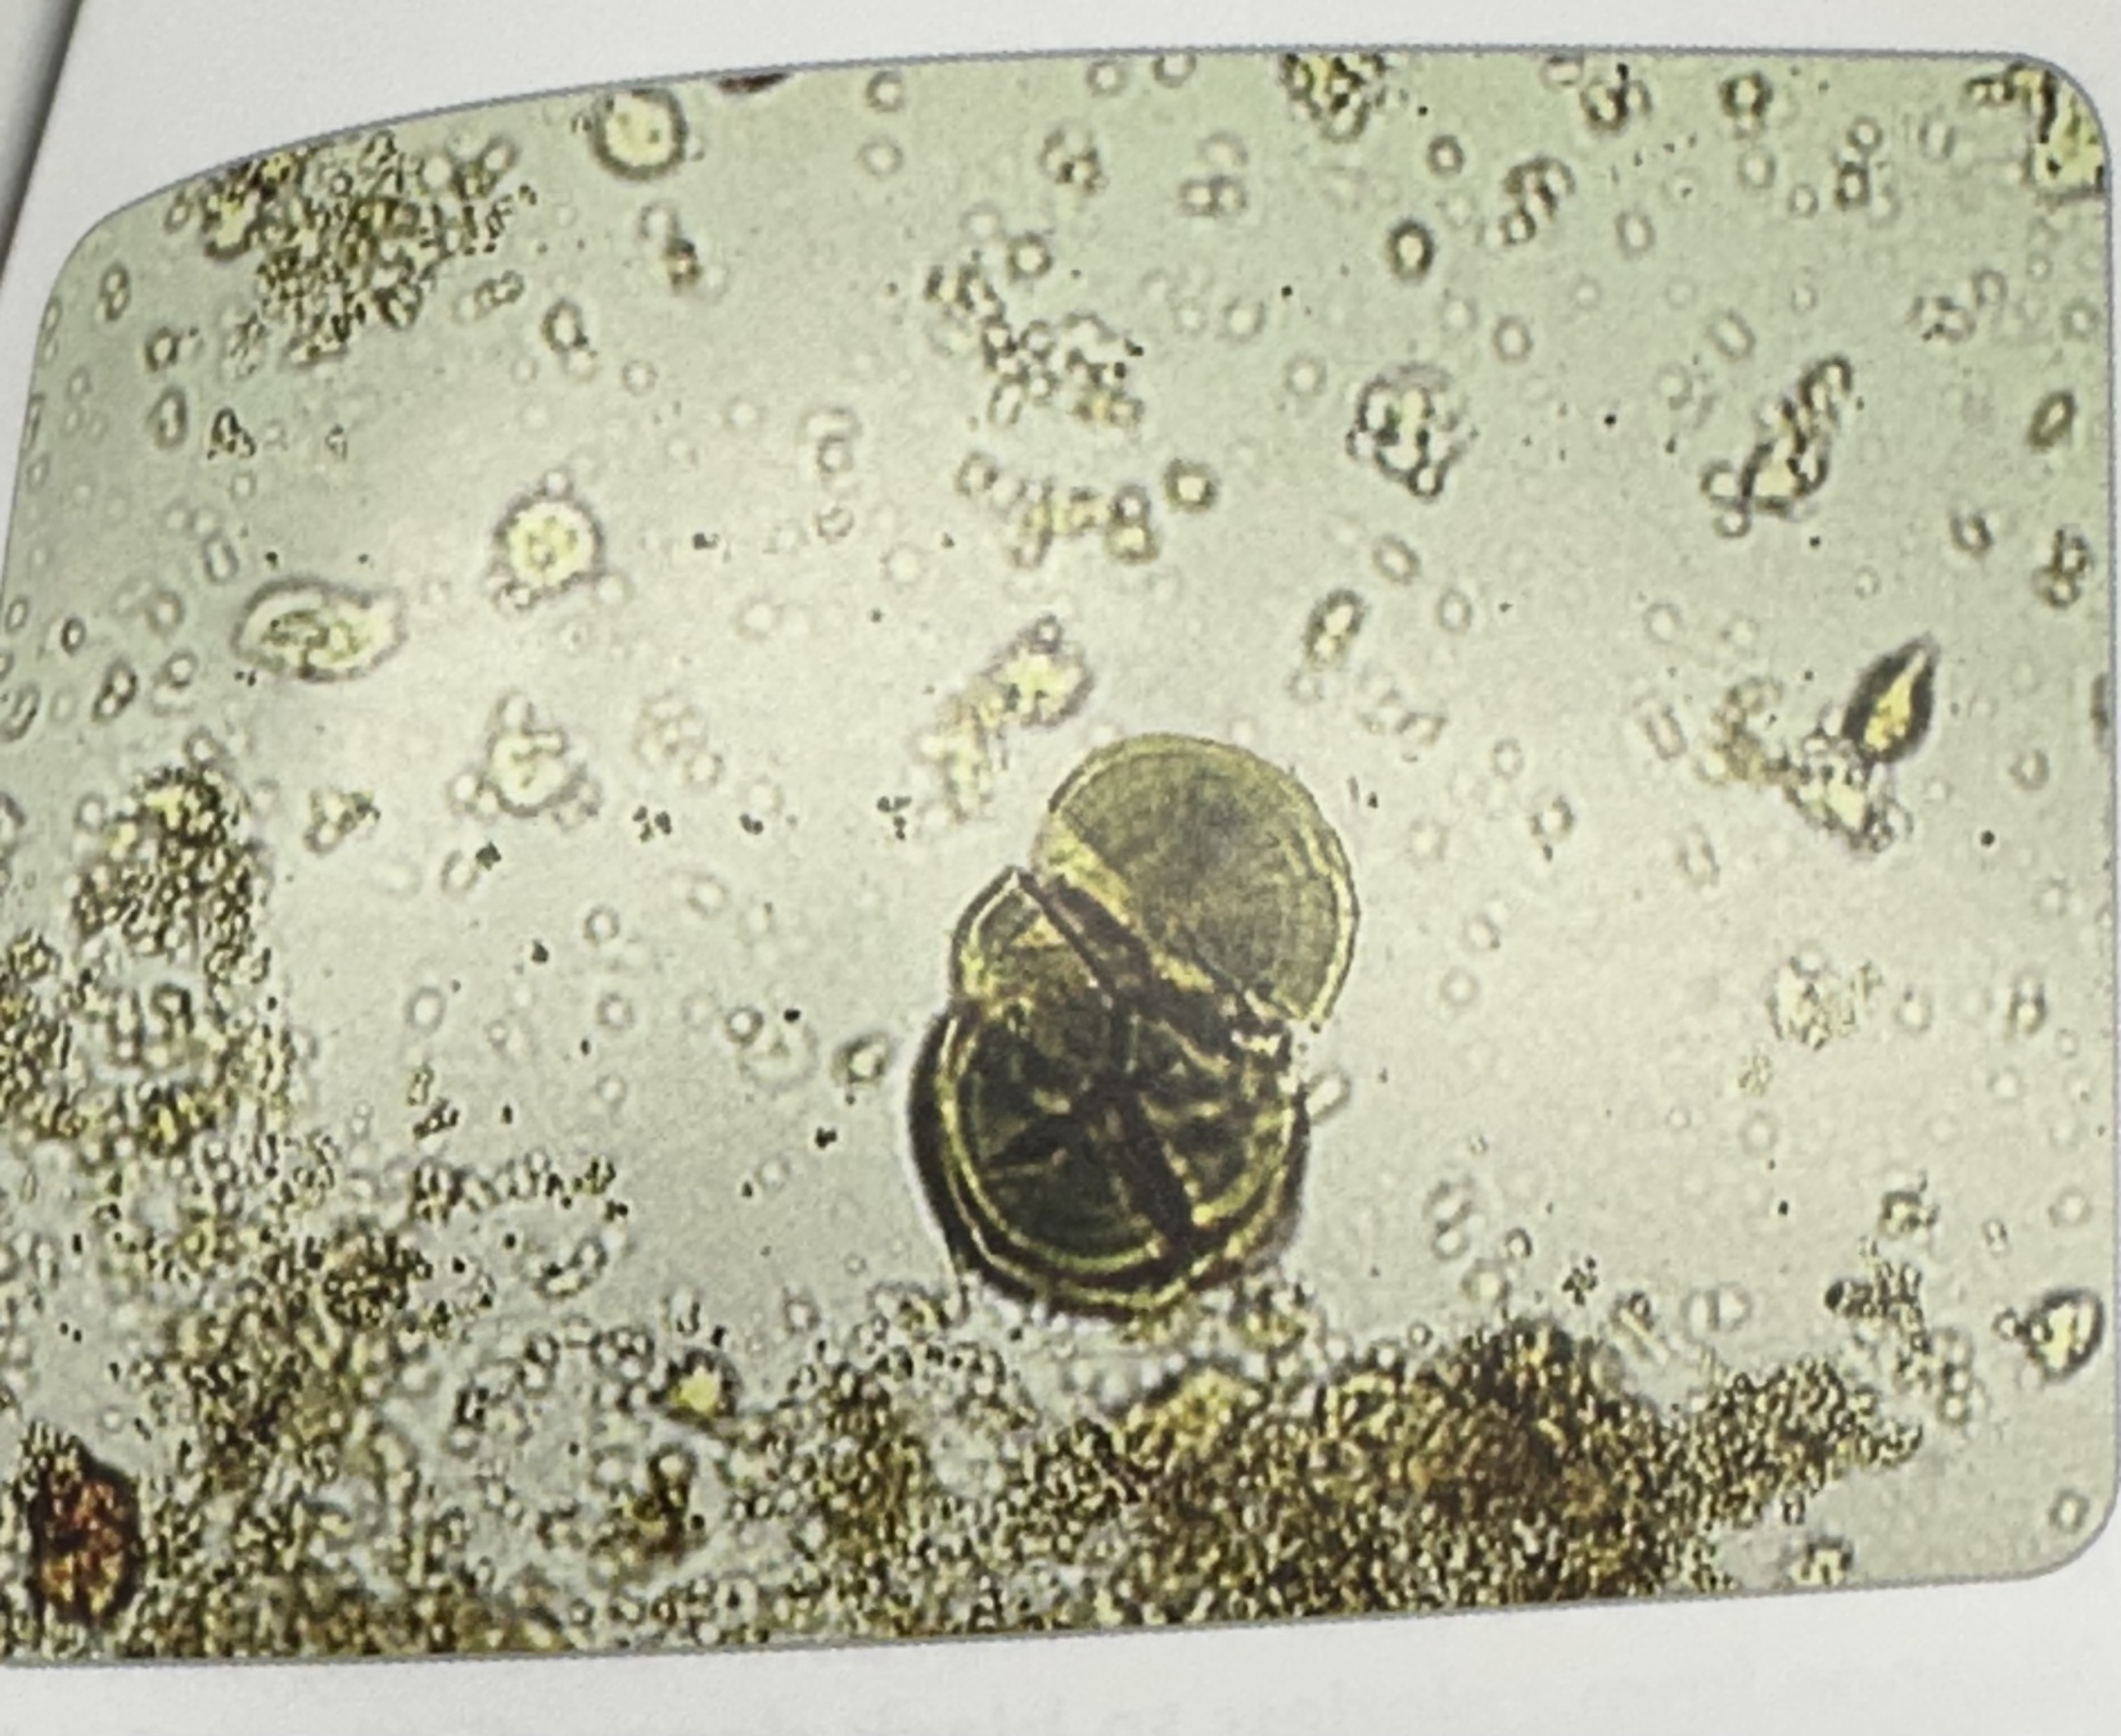

Leucine Crystals

Yellow to brown spheres

Concentric circles and radial striations